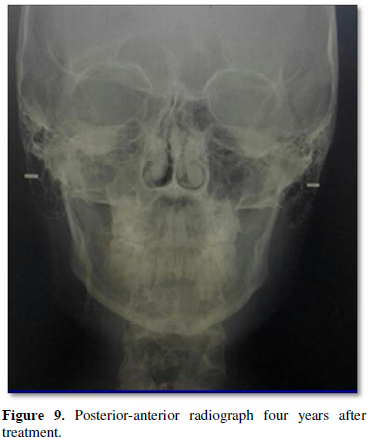

Posterio-anterior (PA view) radiographic demonstrated the significant deviation of the lower third of the face to the left side.

Extra oral photographs (Figure 3) show significant improvement in the facial front and profile and Class 1 facial characteristics after de-bonding. Intraoral photographs (Figure 4) reveal Class I molar and canine relationship, normal overjet and overbite after de-bonding. Figure 5 shows intraoral photos after treatment showing stable results.  Figures 6 and 7 presents extra orally showed significant improved patient front and profile and intraorally stable occlusion four years post-retention. The four years post retention orthopantomograph revealed orthodontic finishing with acceptable parallel root position (Figure 8). The four years post retention posterio-anterior (PA view) radiographic demonstrated significant correction of the asymmetry of the lower third of the face (Figure 9). The cephalometric analysis showed significant changes, presenting a final skeletal Class I pattern (ANB=-0.5°), maxillary/mandibular plane angle 35° within the acceptable range, slightly increased jaw angle 132.5°. Relatively proclined upper incisors (UI to NA 29°) and retroclined lower incisors (LI. to NB 13°) and improved naso-labial angle 117°. DISCUSSION